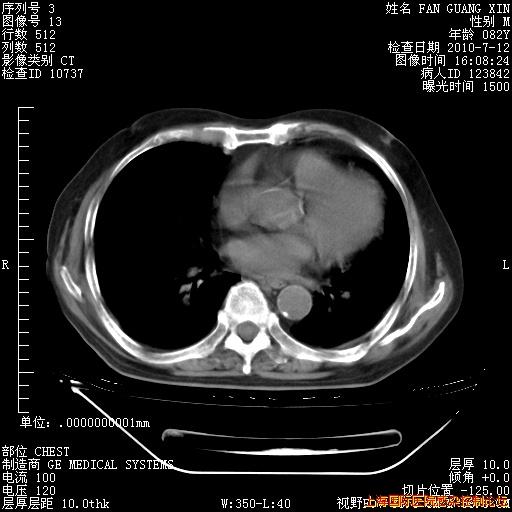

今天复查CT

今天CT